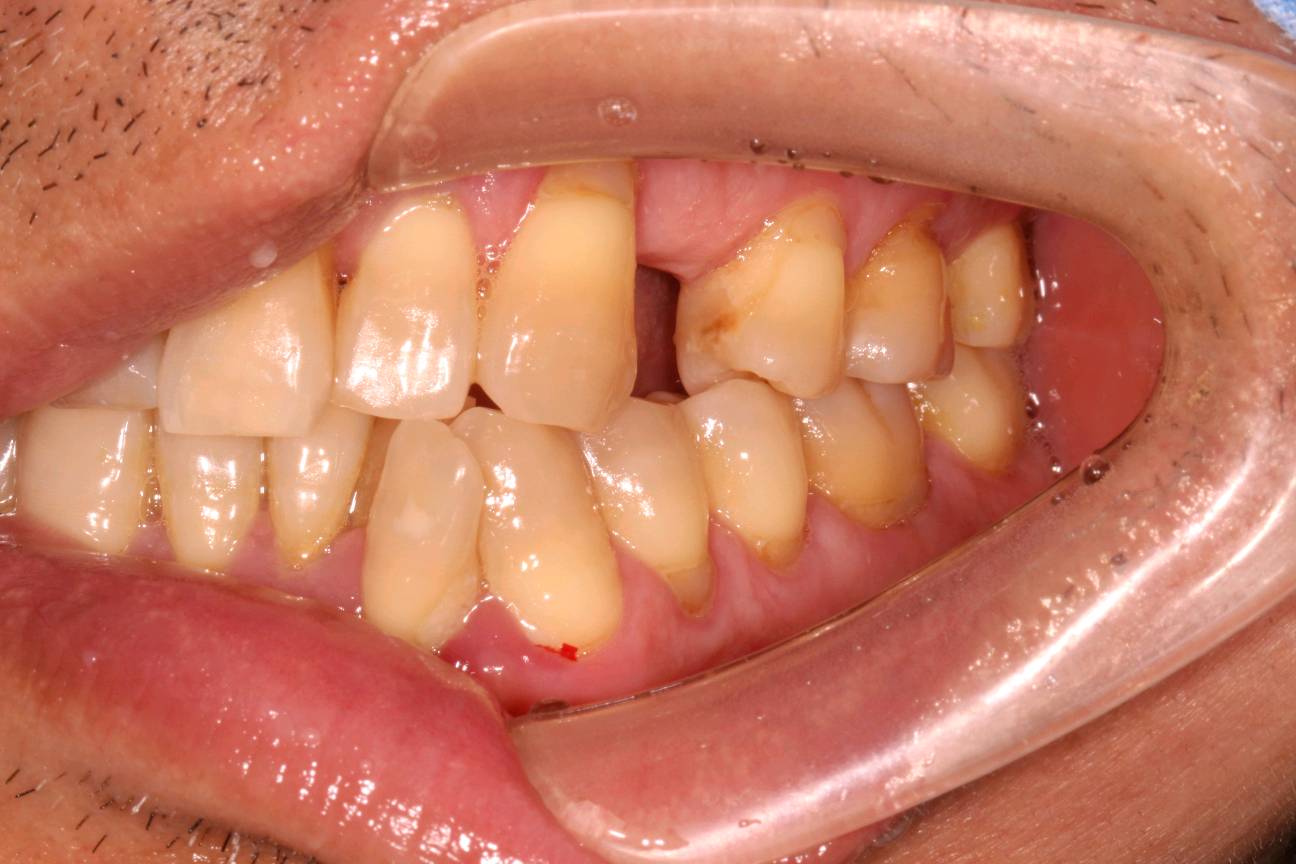

患者男 50 岁,24 缺失,拔牙窝平整,牙龈乳头形态正常,近远中径较宽;唇侧龈缘曲线良好,与邻牙基本协调 。CBCT示:唇侧骨板完整,牙长轴与上颌骨长轴平行。

术前